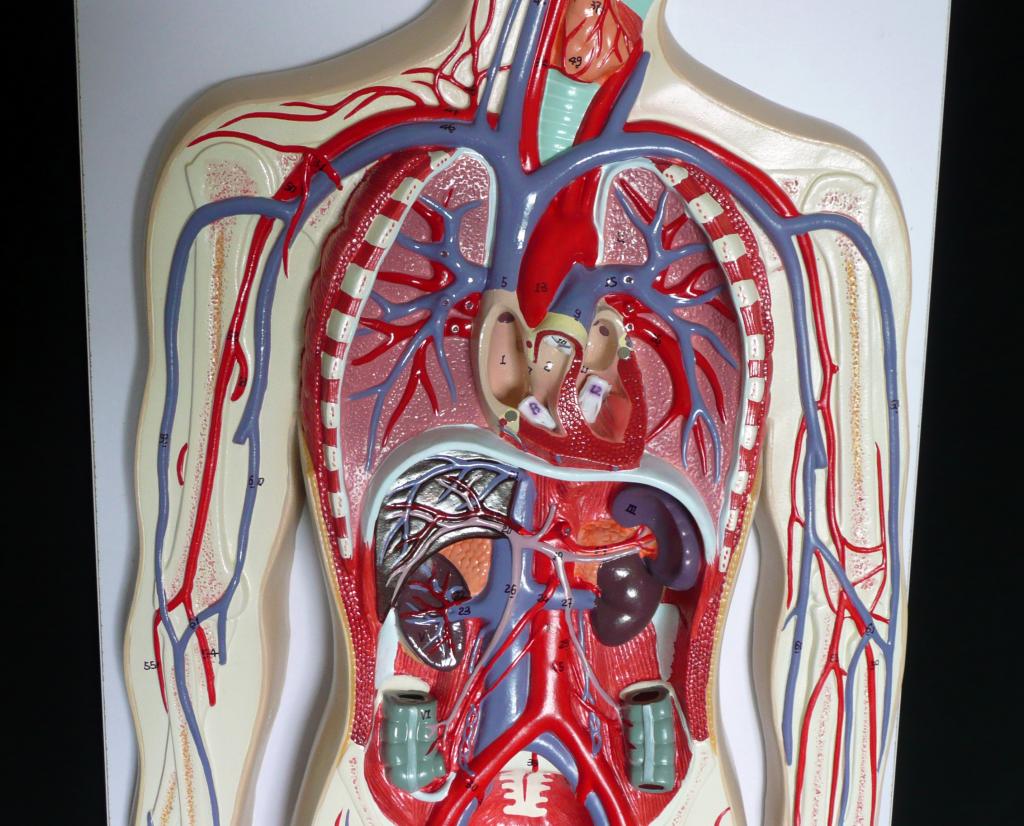

Анатомия человека: кровеносная система и её связь со скелетом

Раздел: Моменты озарения